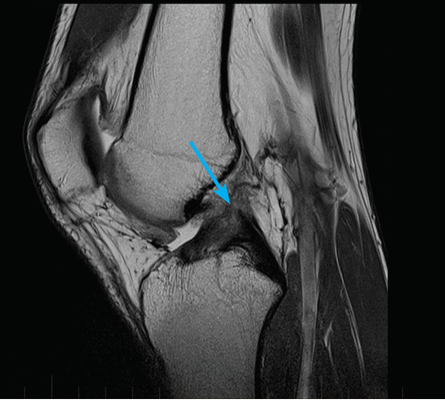

МРТ коленного сустава показывает наличие кисты Бейкера в подколенной ямке (обозначена стрелкой)

Возможно ее обратное развитие вплоть до полного исчезновения, но при условии своевременной диагностики и лечения. При длительном её существовании содержимое кисты затвердевает, формируется спаечный процесс. Возможен ее разрыв, приводящий к появлению острых болей, отеку в подколенной ямке и области голени. В таком случае особое значение приобретает МРТ, которая дает возможность провести дифдиагностику с другими патологиями.